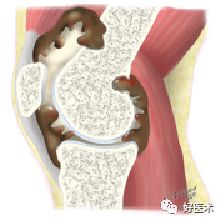

①弥漫型

常表现为受累关节呈周期性、慢性疼痛、肿胀,局部皮温增高但不红,肌肉萎缩,触之有如海绵样或面包样弹性感觉,并有弥漫性压痛,有时在关节周围亦可触及大小不等、基底稍有移动的硬韧结节。在膝关节病例中,有时病变能穿透较薄的关节后侧囊壁,进入腘窝,或沿腘绳肌、小腿肌及股骨与胫骨间的空隙向上下扩展,使膝关节呈弥漫性肿胀。关节积液可抽出黄褐色或血性关节液

受累关节均滑膜肥厚、充血、水肿、部分滑膜破裂在关节内呈纵形裂开、 肥厚 ,并有绒毛和皱襞形成;绒毛呈暗红色或棕黄色,长者如珊瑚状,短者增殖融合呈结节样变,直径1~3cm不等,亦呈红棕色或黄褐色,中老年人伴有不同程度软骨退变